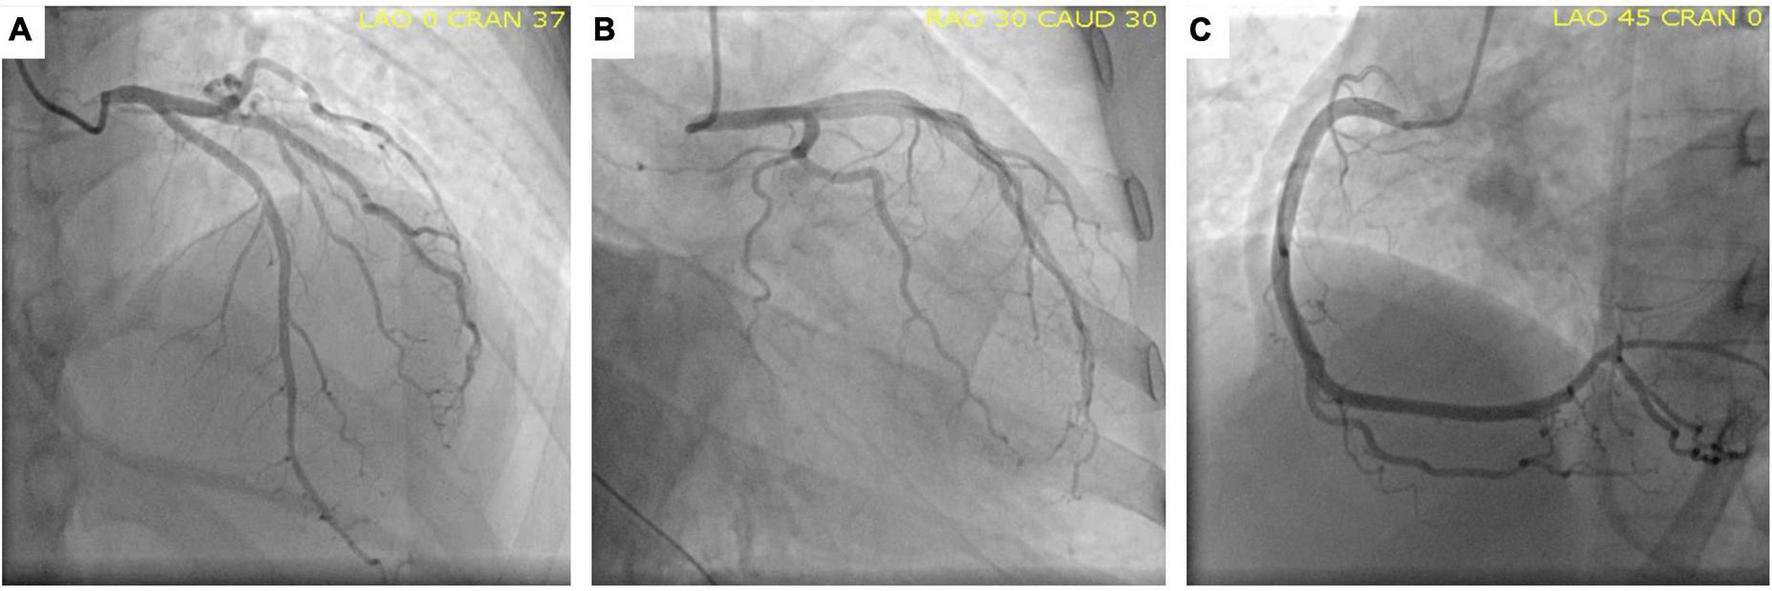

Since a non-ST segment elevation myocardial infarction was the first suspected diagnosis, the patient was taken to the cardiac catheterization laboratory, where the coronary angiogram revealed no significant lesions (Figure 2).

FIGURE 2

Normal coronary angiography. Anterior-posterior cranial view (A), Caudal left-anterior-oblique view (B) and Left-anterior-oblique view (C) showing the circumflex artery, left anterior descending artery, and right coronary artery, respectively, without lesions.